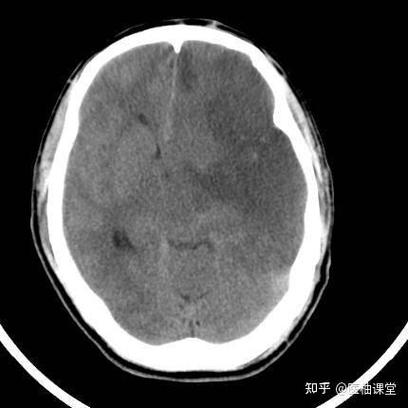

如何“看”一张脑梗CT图片:关键征象

假设你拿到一张疑似脑梗的CT图片(通常是头颅平扫,Axial轴位层面),可以从以下几个方面去观察:

直接征象:脑实质内的异常密度

这是最核心的发现,正常的脑灰质密度比白质稍高,呈浅灰色,而脑脊液是黑色。

间接征象:由脑水肿引起的周围结构改变

当脑组织因缺血而水肿时,它会压迫周围的结构。

脑沟、脑回变浅或消失:

正常脑表面有很多沟回,梗死区域因水肿而肿胀,会把这些“沟壑”撑平,这是非常重要的间接证据。

脑室受压变形、移位:

- 大面积脑水肿会像“水球”一样,将旁边的脑室挤向对侧,导致中线结构移位,这是判断梗死范围大小和严重程度的重要指标。